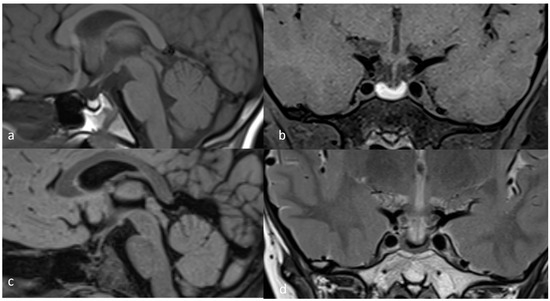

2. Case Presentation